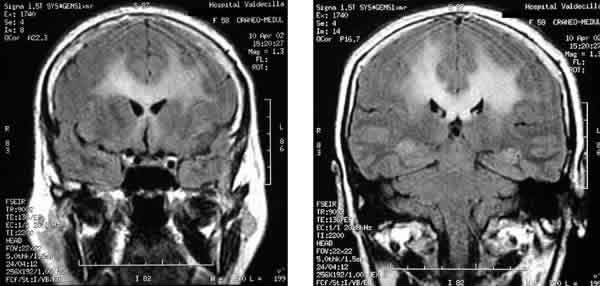

Figs. 5 y 6.